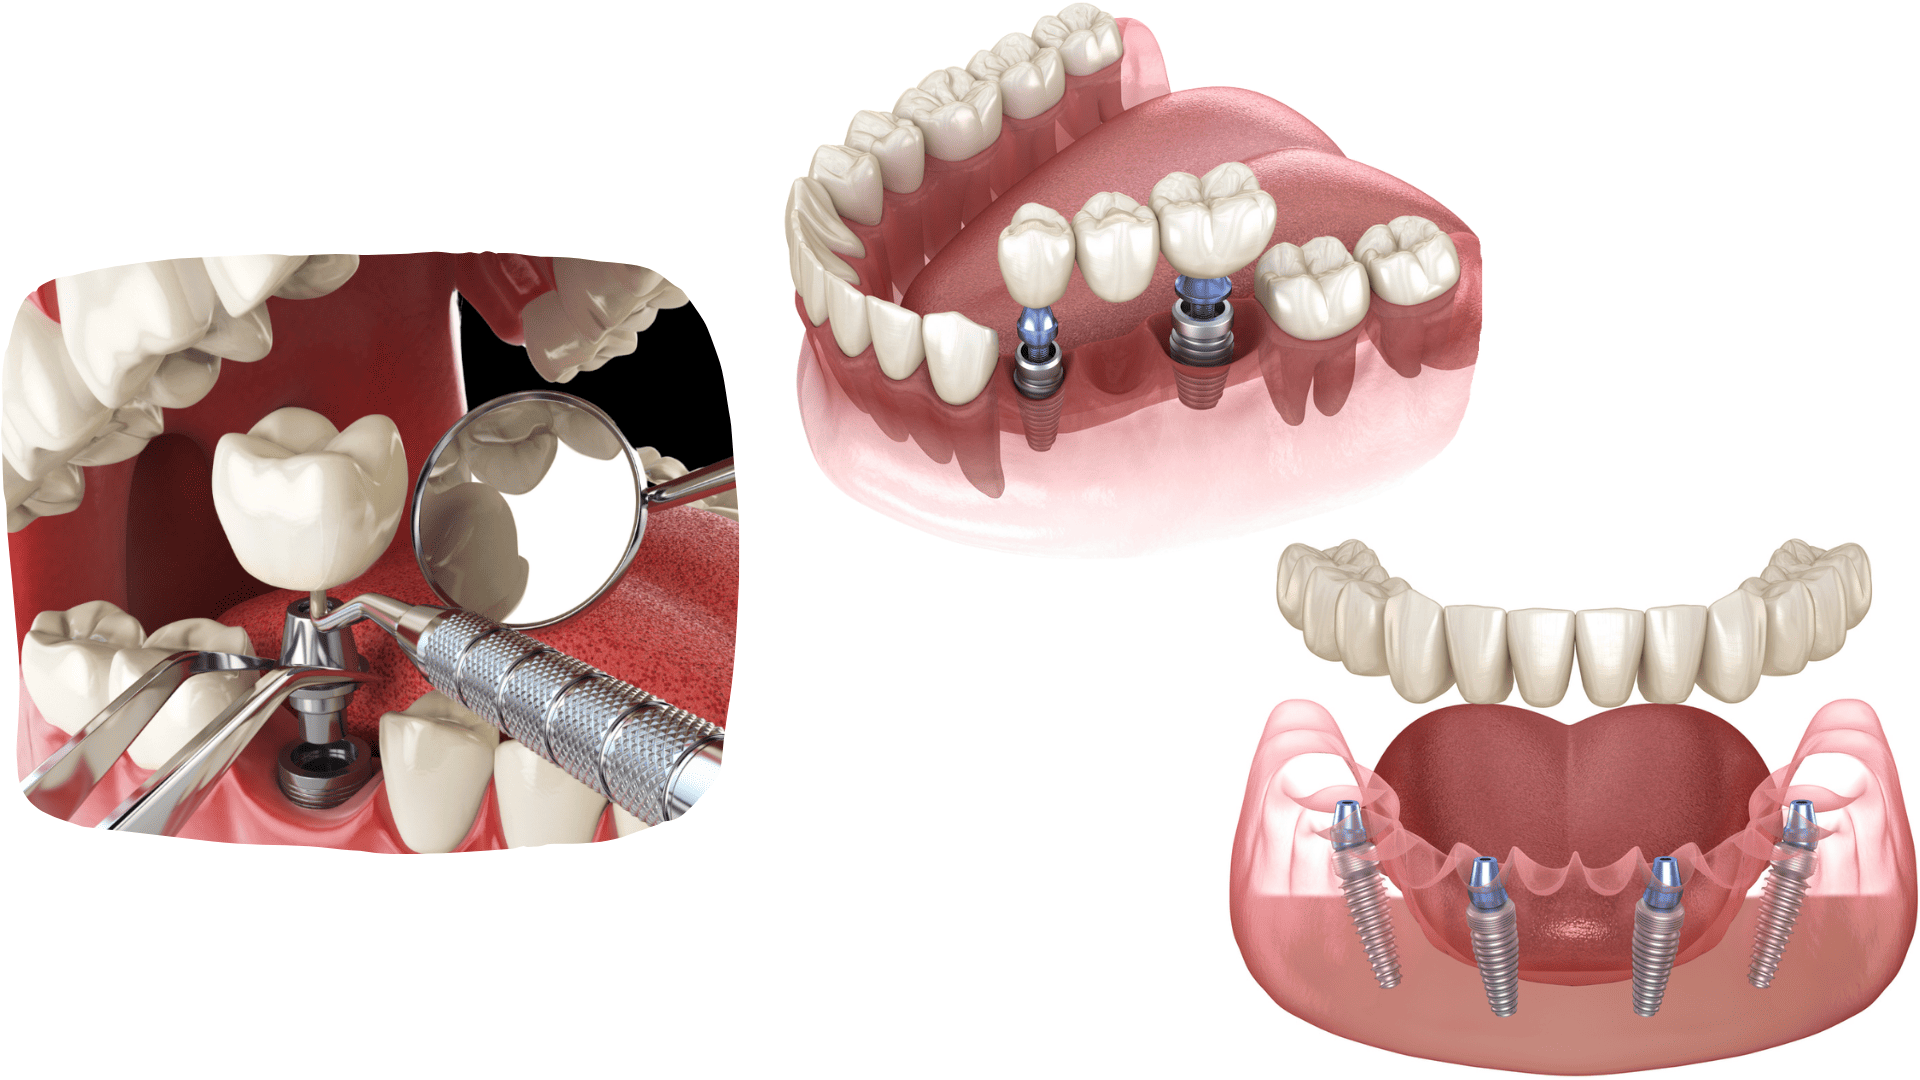

DENTAL IMPLANT PLACEMENT

Dental implant placement is a surgical procedure in which a titanium implant is inserted into the jawbone to replace the natural root of a tooth.

The implant serves as a stable support for crowns, bridges, and prostheses. Titanium is a biologically neutral material that enables firm and permanent bonding of the implant with the bone.

With dental implants, it is possible to replace a single tooth, several teeth, or to address complete edentulism.

With dental implants, it is possible to replace a single tooth, several teeth, or to address complete edentulism.